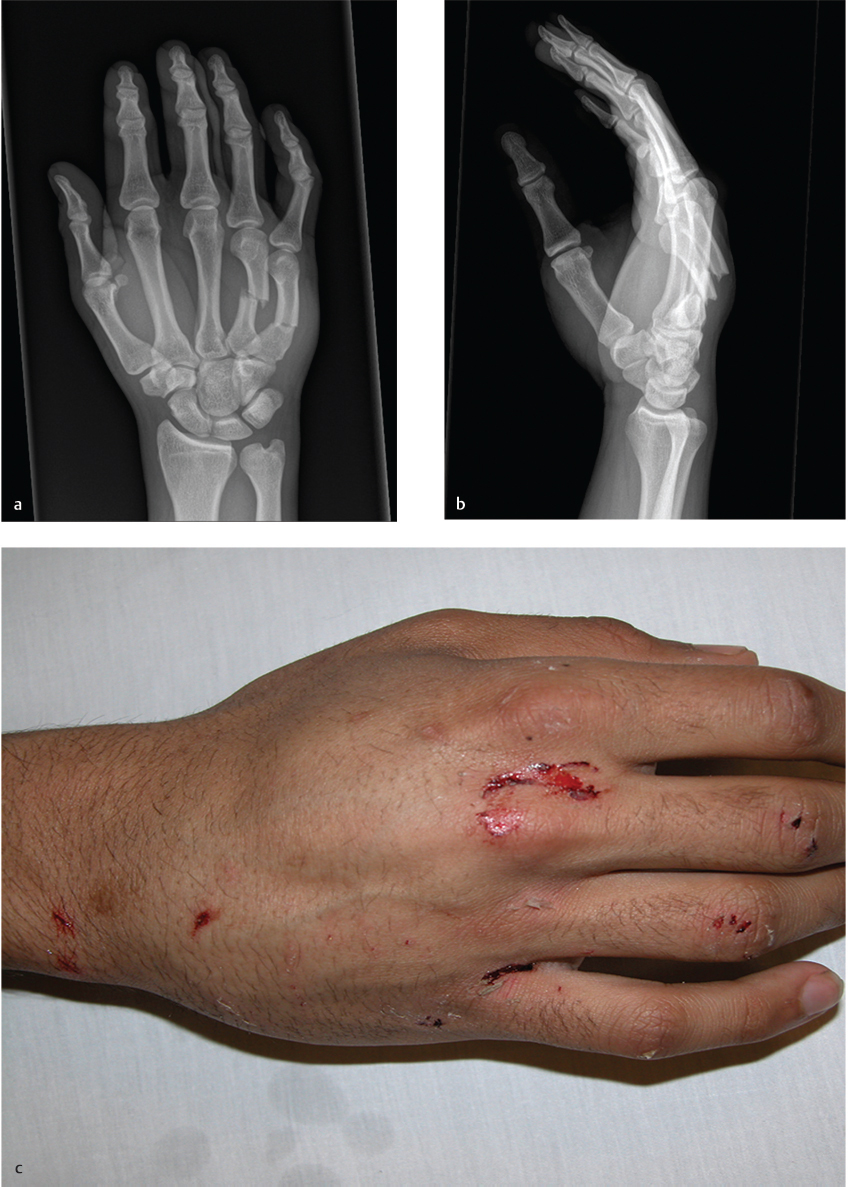

Transverse fractures of the ring and small finger metacarpal shafts with angulation, rotation, and shortening of the affected digits

Dorsal prominence of the hand secondary to dorsally angulated fractures

Standard three-view X-rays (anteroposterior, lateral, and oblique) of the hand should be obtained to assess the fracture or presence of foreign bodies